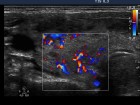

Ultrasonography: Both lobes were enlarged, moderately hypoechogenic, inhomogeneous and displayed increased vascularization.

Follow-up examinations (rows from 1st to 8th):

Corresponding sonographic images (row)

2. Note the relation between volume, echogenicity, vascularization and hormone levels.